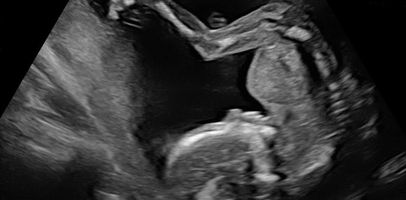

Such changes may help to diagnose health problems including cancer. Sonography specialists accessible through doctors in italy provide a full range of ultrasound diagnostics. Ultrasound is a non-invasive scan used to monitor and diagnose conditions in many parts of the body.

About free ultrasound scan. An ultrasound scan is pain-free and can take from 15 to 30 minutes depending on the part of the body being scanned. Must be at least 13 weeks 5-10 minute ultrasound 2D3D4DHD LIVE.

Pin By Drrupesh Senapati On Formula 1 Blackbox Airdrop My. Contact a location near you for products or services. Ultrasound is an ideal imaging technique for pregnancy diagnosis and monitoring since the fetuses can be seen in.